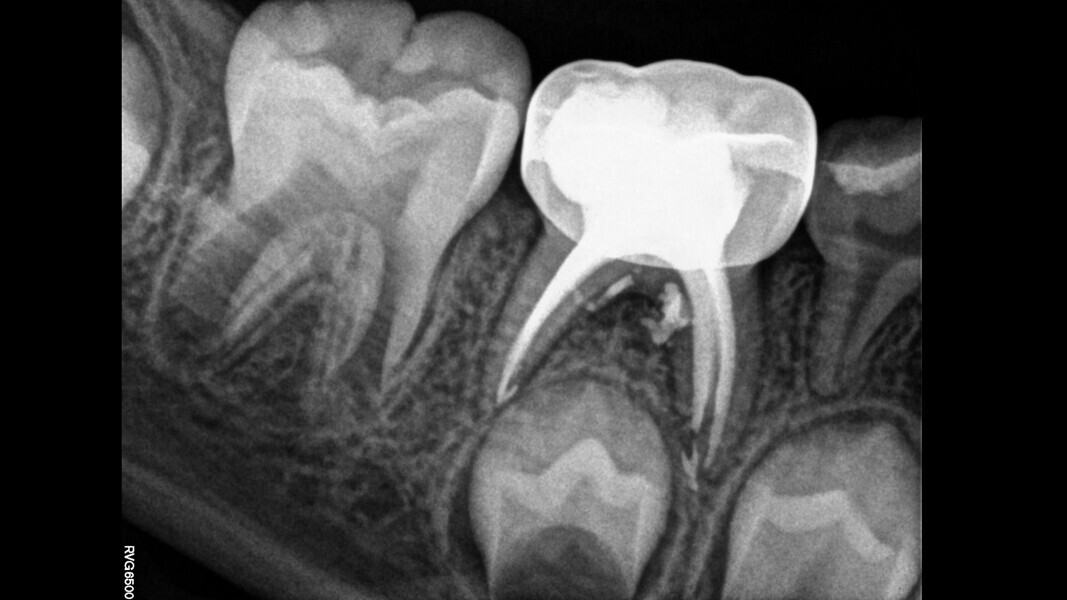

Case 2 (Figs. 5–9)

This male patient was 6 years and 7 months old and presented with severe tooth decay on the mandibular left first primary molar without any symptoms of pain. He experienced slight discomfort to percussion and palpation of the buccal gingiva. A buccal abscess and no mobility were observed. The radiograph showed a large area of interradicular bone loss. The tooth was diagnosed with pulp necrosis and an asymptomatic apical abscess. Pulpectomy was performed, and at a second appointment, a stainless-steel crown was placed upon confirming absence of signs or symptoms of disease. At the 14-month recall, no clinical pathology was detected and a normal eruptive process of the permanent premolars was observed in spite of the extrusion of the obturation material.